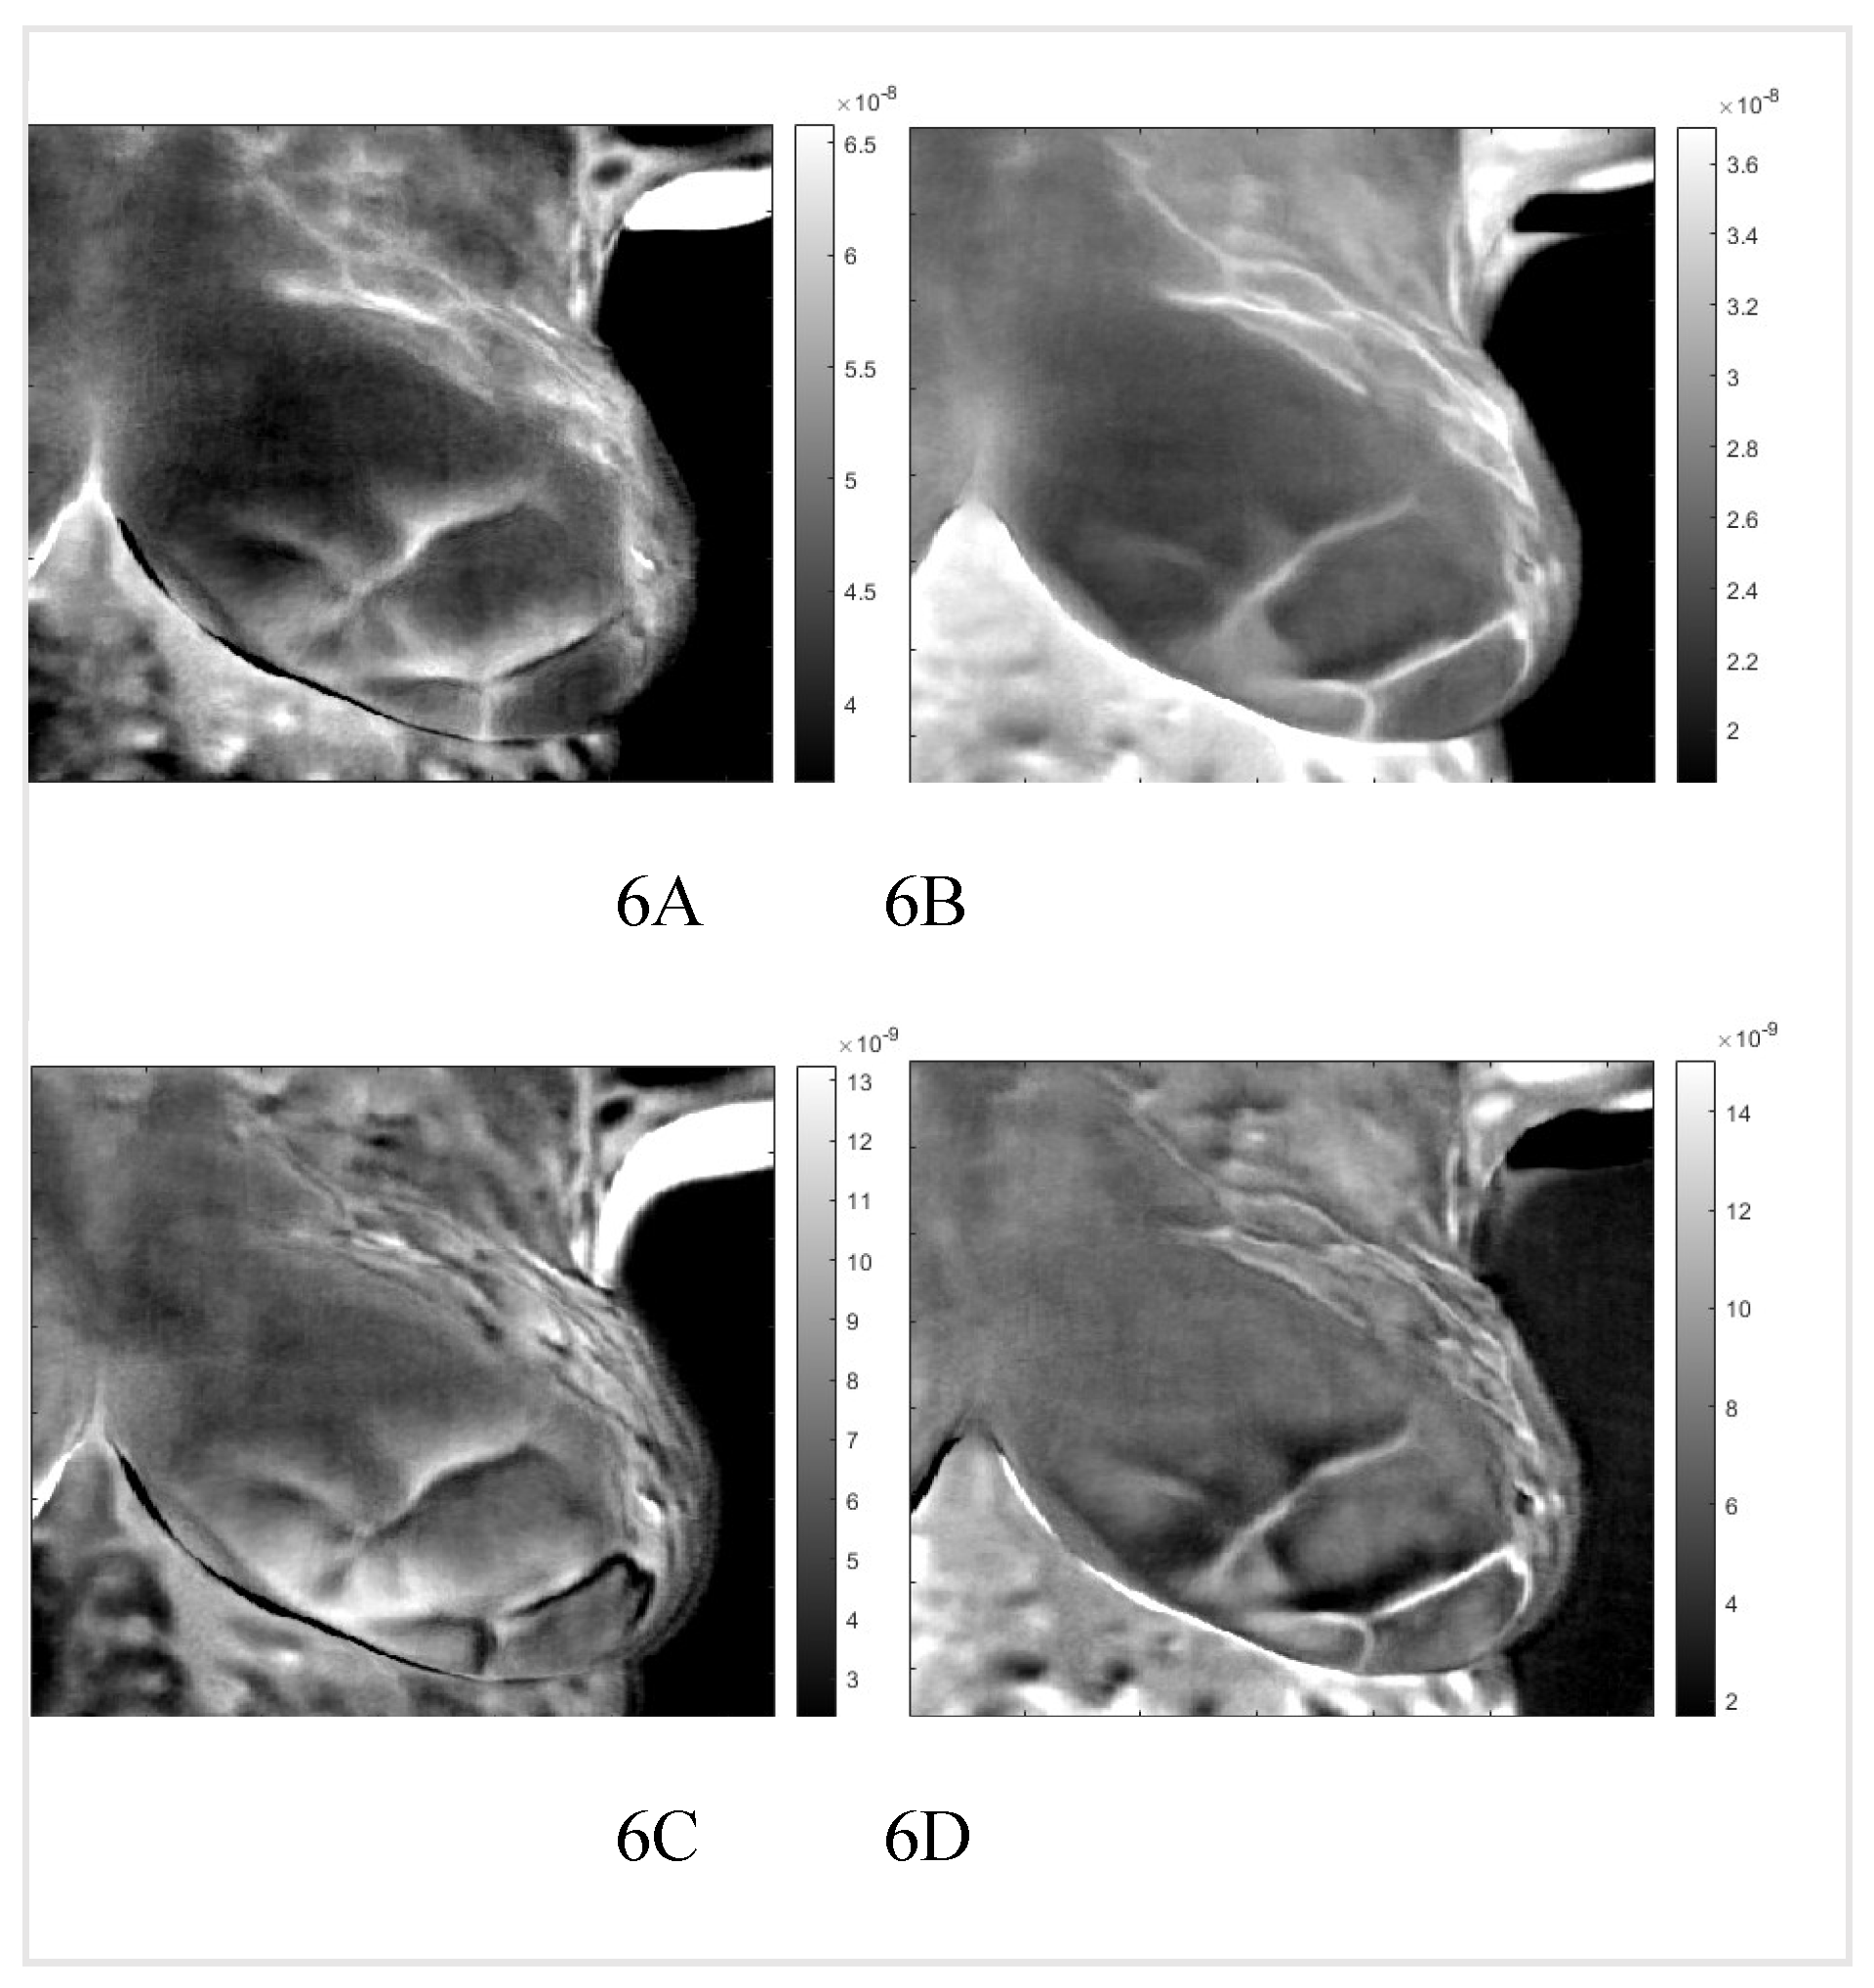

By applying the inverse transformation to the images 2-1 to 2-4, we get the images in Figure 5. In Figure 6, we present the result for the left breast, labeled "sick," and patient #T285 in Figures 7-1 to 7-4 for the left breast, labeled "healthy," and for the right breast, labeled "sick," in Figure 8. The supplemental material presents process images of patients #282 and #286.

Figure 7. “Healthy” left breast of patient #T285. Images 1: to 4 after application of the inverse PCI transform. 1 and 2 are images of thermal reflection, while 3 and 4 are images of vasoconstriction.

Preprints 68607 g007

Figure 8. “Sick” left breast of patient #T285. Images 1: to 4 after application of the inverse PCI transform. 1 and 2 are images of thermal reflection, while 3 and 4 are images of vasoconstriction.

We identified two very similar thermal images at each breast. The first image is at the same polarity as the external cooling. The second image is from twice the depth of the first one and at the opposite polarity. Our interpretation is: The first reflection is due to vasoconstriction, while the second is due to thermal reflection. Skins nerves trigger vasoconstriction, which results in almost instantaneous constriction. The response to external cooling as a thermal regulation mechanism is the reduction of the heat conduct out of the vascular system, which is at the same polarity as the external cooling. The heat propagates only one way from the vascular system to the skin. Response by thermal reflection is different; the cooling traverses from the skin to the blood vessel, then reaches a constant temperature boundary, blood flow, and propagates back to the skin. The outcome is a signal with the reverse polarity of the cooling at twice the time of the first image. Figures six to eight show reflected heat in images one and three, while images two and four show vasoconstriction-generated signals. Comparing the images of the healthy and sick breast, we notice that the two images of reflection and vasoconstriction of the healthy breast are almost identical; on the other hand, in the sick breast, we can see a difference: Some of the vessels in the vasoconstricted images are not visible or are at reduced intensity; they barely constrict in comparison to a healthy one. We noticed similar behavior in the supplemental images. This reduced constriction might be highly significant as it could be helpful in cancer screening. Remember that the data set had only four image sequences identifying the sick breast.